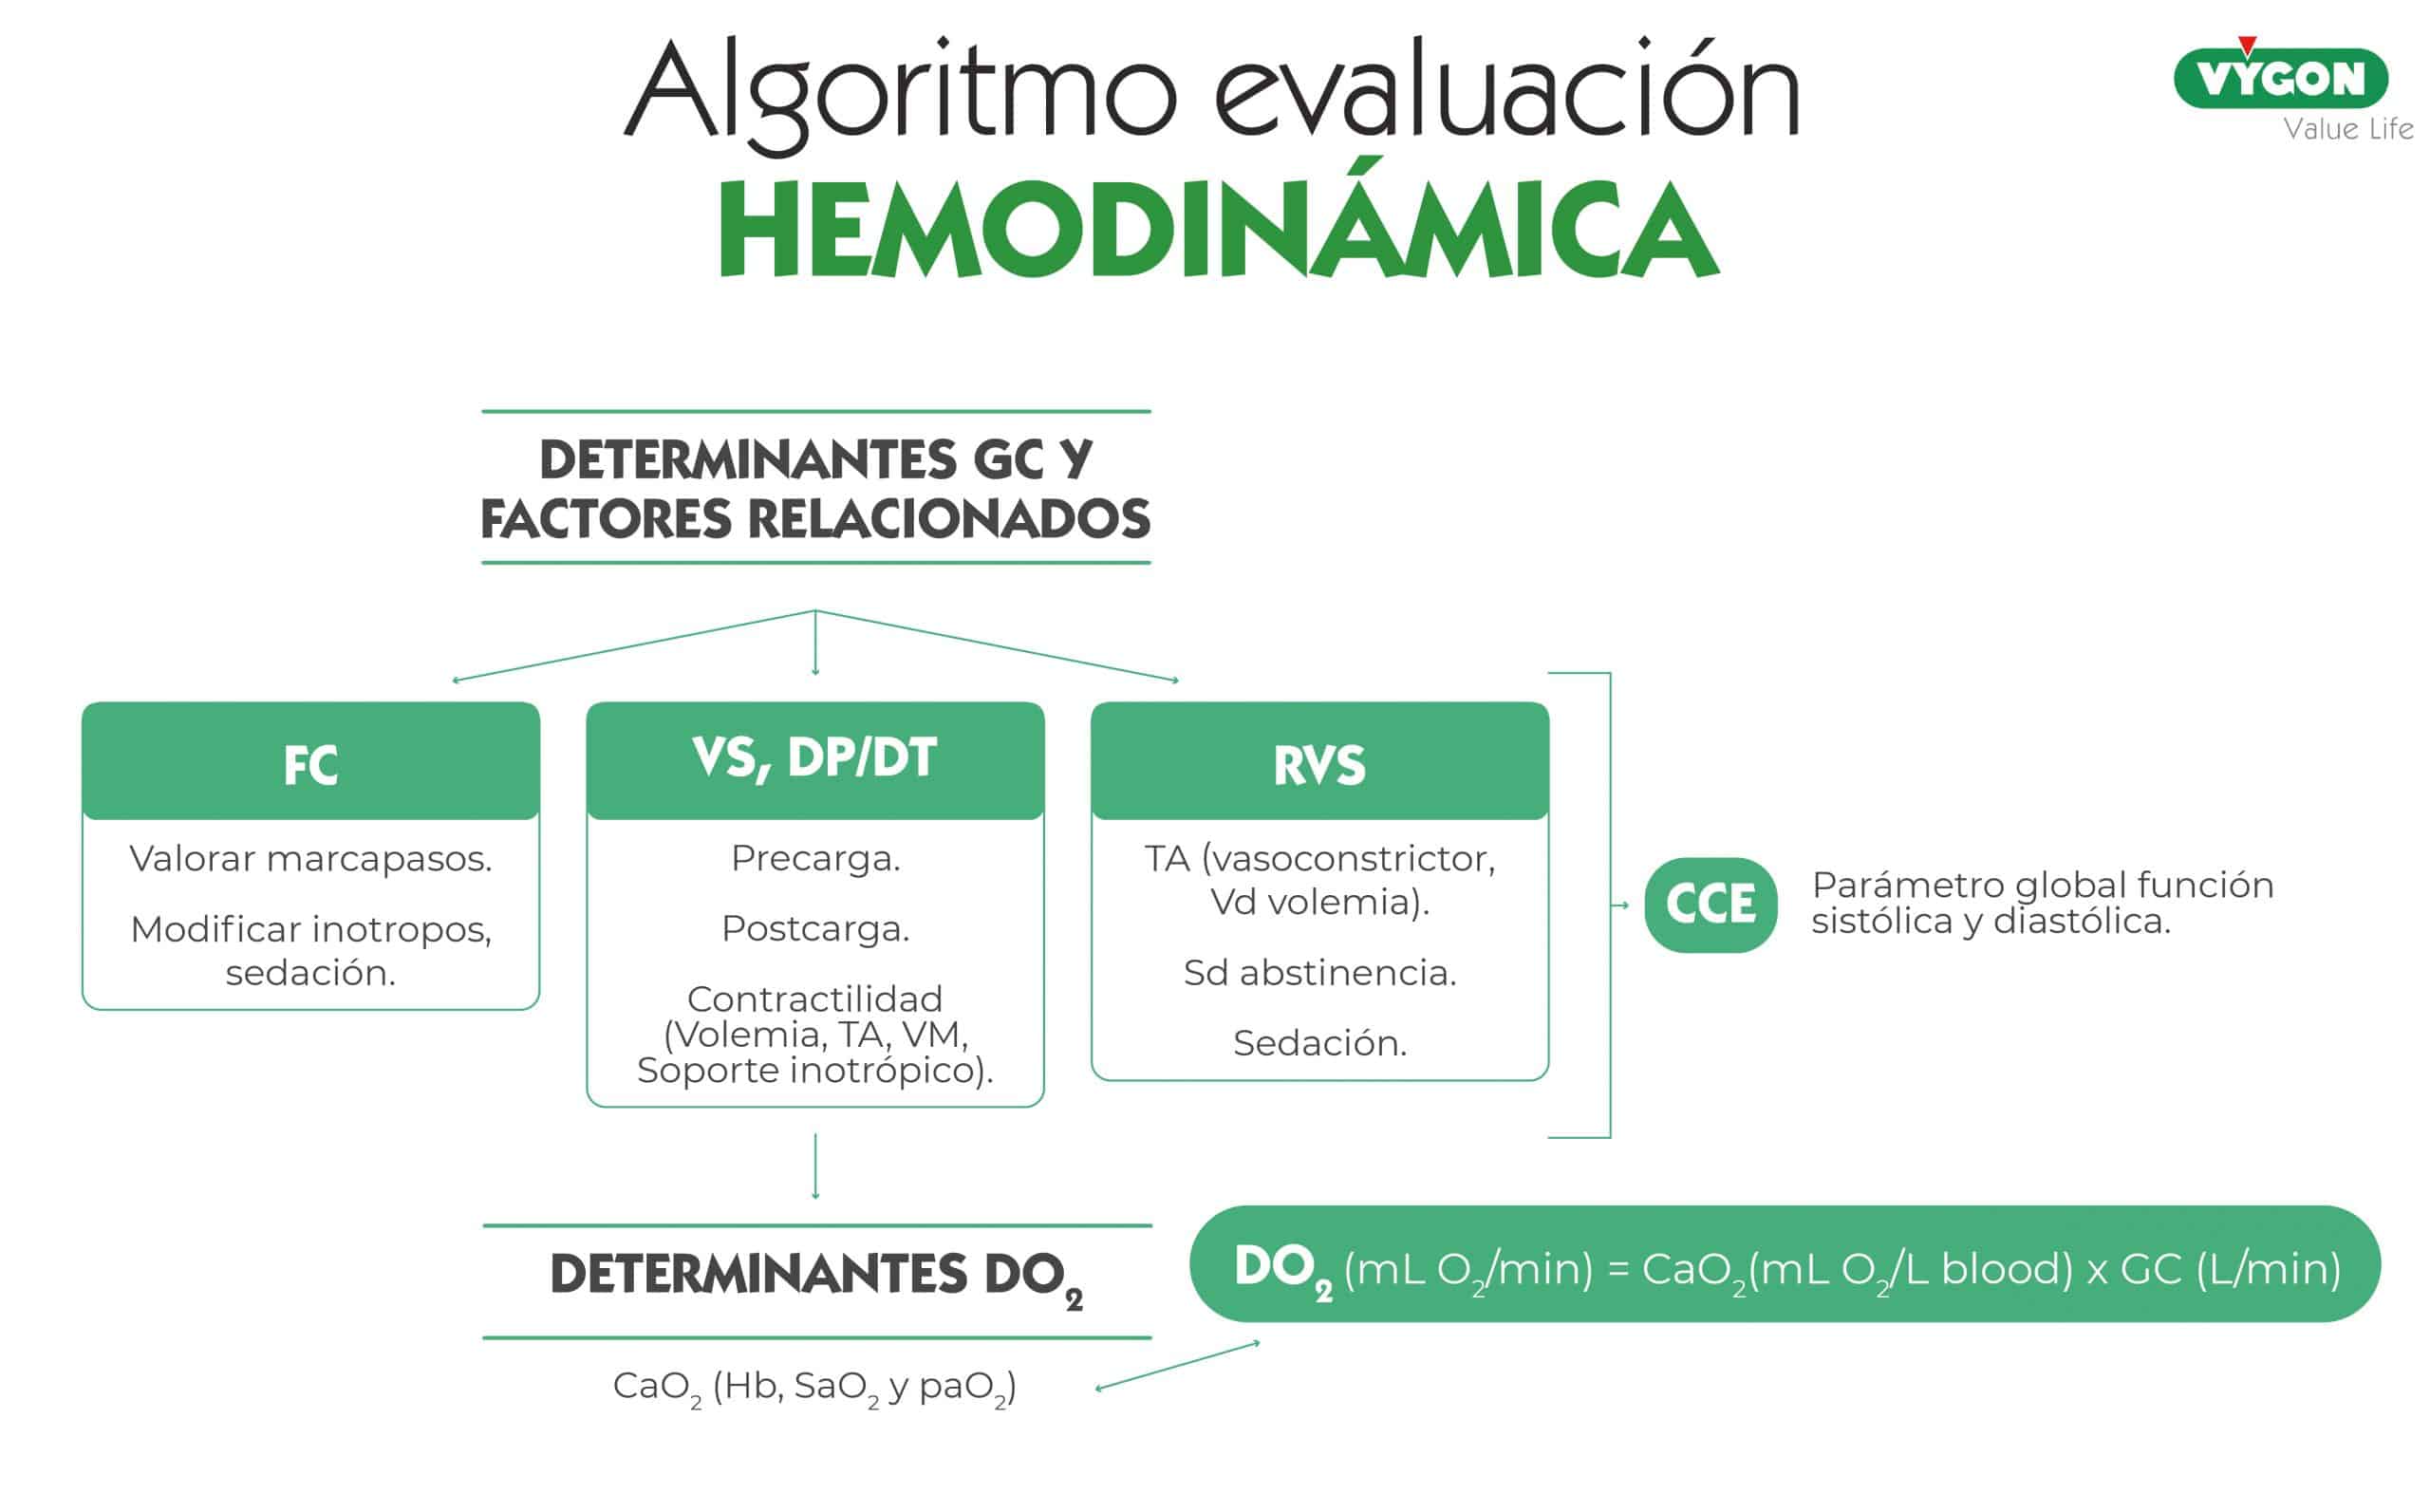

¿Por qué monitorizar?

La monitorización hemodinámica es esencial para realizar un tratamiento apropiado dirigido por objetivos terapéuticos en los pacientes críticos, entre los que se encuentra el postoperatorio de cirugía cardiaca.

La monitorización continua y en tiempo real es imprescindible para la adecuada interpretación y la anticipación en el manejo clínico.

El gasto cardíaco tiene que adaptarse a las necesidades de consumo de O2 en cada momento. El paciente crítico tiene unas demandas de O2 anormales debido al proceso de la enfermedad y la fisiopatología de su propia cardiopatía, como sucede en el ventrículo único.

Es fundamental integrar la fisiopatología del paciente con la situación clínica y los objetivos terapéuticos.

En la pantalla del monitor se observó, como se puede ver en la imagen:

- Índice cardiaco (IC) de 2.1 /min/m2

- Volumen sistólico (SV) de 18 m/m2

- Resistencia vascular sistémica (SVR) de 1.700 dynas·seg3/cm3

- dP/dtmáx. de 0.9 mmHg/ml

- Ciclo de eficiencia cardiaca (CCE) de -0.18

- DO2 de 110 ml/min

- Resistencias vasculares sistémicas (RVS) estaban elevadas debido a la vasoconstrición e hipertensión: se intensificó el tratamiento vasodiatador.

En pacientes similares al del caso clínico, resulta de gran importancia el control de síntomas de síndrome abstinencia, principalmente en neonatos y lactantes pequeños, ya que puede provocar gran hipertensión, taquicardia y la situación de llanto aumenta mucho las resistencias vasculares sistémicas. Por lo tanto, monitorizar la RVS nos puede ayudar a anticiparnos. - Variación del volumen sistólico (VVS) y dP/dt máx.: se debe optimizar la precarga para evitar que sea un paciente hipovolémico; además estos pacientes tienen congestión pulmonar y debemos tratarle con diurético.

Con respecto al soporte inotrópico, trataron de no soportar demasiado con adrenalina, ya que aumenta las resistencias y la frecuencia. - Ciclo de Eficiencia Cardíaca (CCE): se trata de un parámetro que aporta mucha información sobre la interacción ventrículo-arterial y de un ventrículo con otro, siendo un parámetro muy importante, sobre todo en la disfunción diastólica, ya que permite controlar factores agravantes como la taquicardia y la hipertensión arterial.

La doctora comenta que siempre monitorizan los siguientes parámetros claves:

- Índice Cardíaco (IC)

- Volumen sistólico (VS)

- Resistencias vasculares sistémicas (RVS)

- Eficiencia del Ciclo Cardíaco (CCE)

- Dp/dt máx.

- Elastancia dinámica (VVS/PPV)

- Aporte de Oxígeno (DO2)

Estos parámetros permiten anticiparse y evitar un bajo gasto.